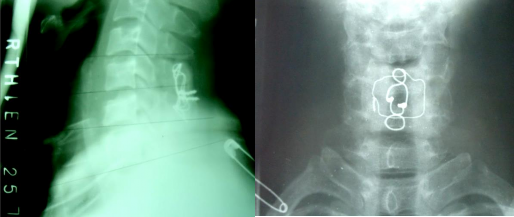

BÁN TRẬT C5-C6 (8-4-2003)

Mỏm khớp dưới cởi lên đỉnh mỏm khớp trên.

C5 di lệch ra trước. Gập góc mở ra sau. SAU MỔ: Nắn, cố định tốt